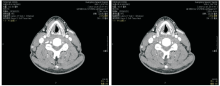

2012-05-18喉部增强CT:喉癌术后, 左侧舌骨术后改变, 与2010-12-28 CT对照, 原左侧声带小结节消失, 新增左侧声带中部小结节, 见图2和图3。诊断:左侧声门型鳞状细胞癌术后局部复发rT2N0M0 Ⅱ 期, 无病生存期17个月, 建议进一步检查。